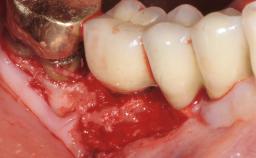

Resective Surgical Treatment of Peri-Implantitis Including Implantoplasty

In this case, Myroslav Solonko, Ignacio Sanz Sánchez and Mariano Sanz present a treatment that aims to eliminate exposed implant threads by modifying the implant surface, converting a moderately-rough surface into a smooth surface.

A 63-year-old male patient was referred to the post-graduate periodontal clinic of the Complutense University of Madrid for the treatment of peri-implantitis. According to the patient’s record, all his maxillary teeth had been extracted ten years previously due to severe periodontitis, and a full-mouth implant-supported restoration on eight implants was placed. No supportive periodontal therapy was provided apart from occasional check-ups by the restorative dentist.